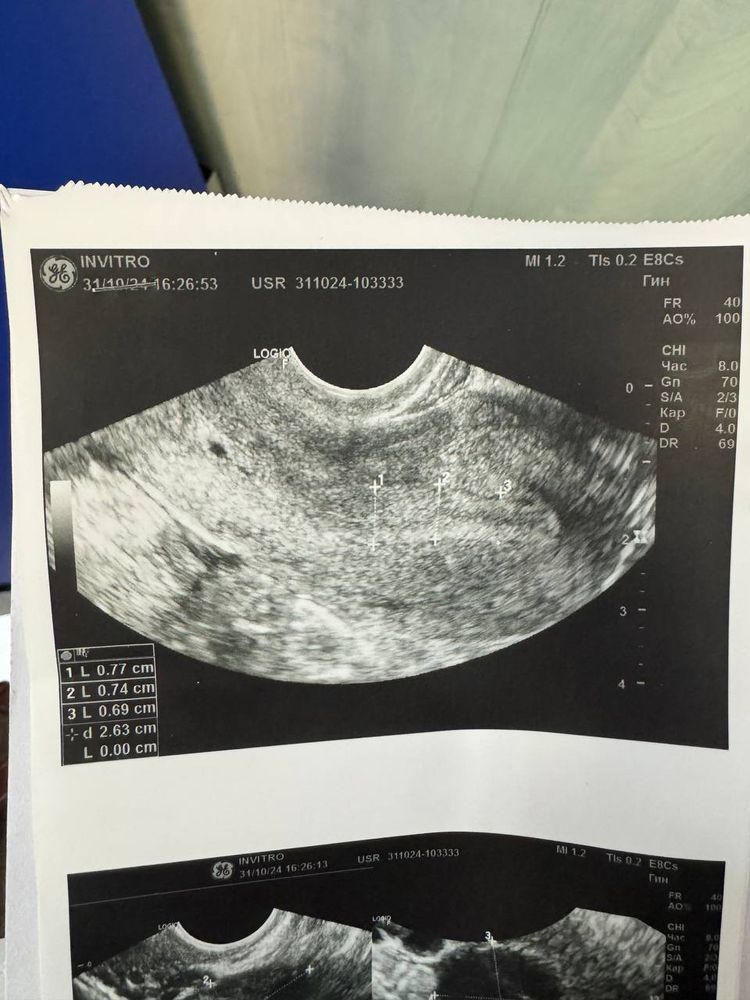

Девочки,помогите пожалуйста. Я третий цикл принимаю инозитол, на двух циклах овуляция была на 18ДЦ, в этот раз пошла на УЗИ на 17ДЦ и врач сказала ,что видит хорошее ЖТ и что овуляция уже была,конечно примерно когда она была не может сказать. У меня сейчас идет 34 ДЦ, грудь ужасно болит, всю неделю подтягивал низ живота как будто сейчас польет и белые выделения. Но,месячных нет( сделала тест вечером он показал одну полоску( конечно наверное лучше делать тесты утром). Не могу понять, что со мной. Может у кого так было ?